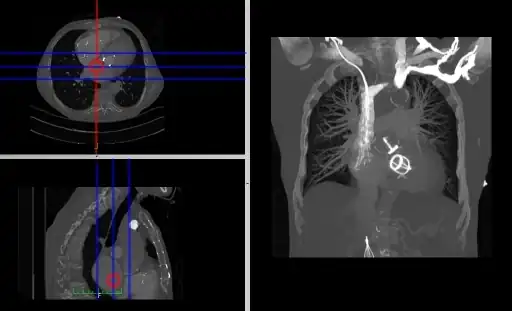

- Coronal and sagittal reconstructions are referred to as Orthogonal MPRs because the perspectives generated are from planes of image data which are at right angles to each other. Composite MPR displays can be generated so that linked cursors or crosshairs can be used to locate a point of interest from all three perspectives, as illustrated in these images:

![]() |

- This form of image presentation is sometimes referred to as a TCS display – implying the viewing of Transaxial, Coronal and Sagittal slices. It can be combined with the slice projection methods we discussed earlier, as illustrated in the two sets of images below, where the blue lines highlight the limits of the coronal projections:

- Oblique MPRs are possible by defining angled planes through the voxel data , as illustrated in the following figure:

- Here the plane can be defined in, say, the axial images (red line, top left) and a maximum intensity projection (the limits used are highlighted by the blue lines), for example, can be displayed for the reconstructed plane (right). This technique is useful when attempting to generate perspectives in cases where the visualization of three-dimensional structures is complicated by overlapping anatomical detail.

- Curved MPRs can be used for the reconstruction of more complex perspectives, as illustrated in the next figure:

- Here a curve (highlighted in green) can been positioned in the axial images (left panel) to define a curved surface which extends through the voxel data in the z-direction, and voxels from this data can be reconstructed into a two-dimensional image (right panel). Note that more complex curves than the one illustrated can be generated so that, for instance, the three-dimensional course of a major blood vessel can be isolated, or CT head scans can be planarized for orthodontic applications.